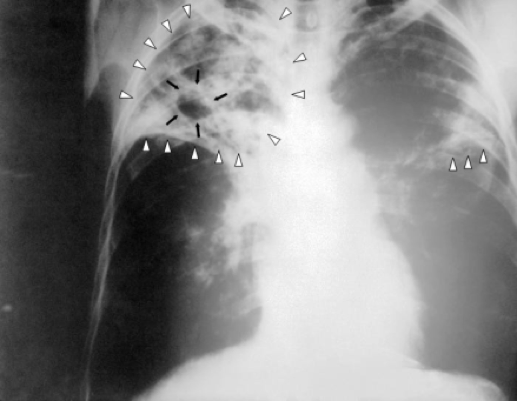

Imaging

- Chest X-ray (CXR):

- Upper lobe consolidation

- Ghon focus/complex

- Cavitary lesions (reactivation TB)

- Miliary pattern (in disseminated disease)

Ghon Focus and Ghon Complex

- Ghon focus: 1–1.5 cm area of gray-white inflammation with caseous necrosis

- Ghon complex: Ghon focus + involvement of regional hilar lymph nodes